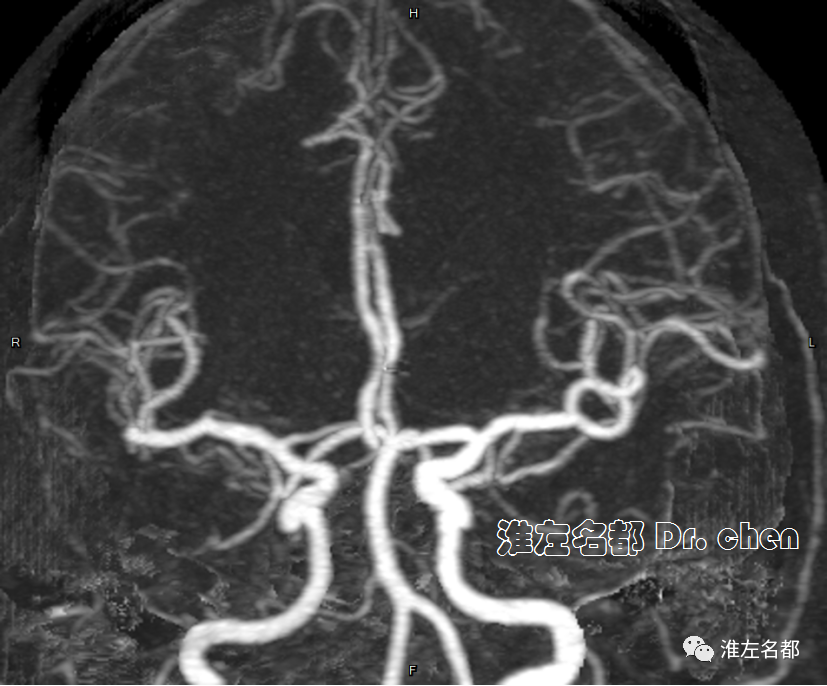

△头颅CTA:左侧大脑前动脉A2段远端闭塞(橙箭)。

△颈部CTA:左侧颈内动脉颅外段螺旋样延长迂曲(白箭)。

△颅脑CTA:左侧大脑前动脉A3段狭窄(橙箭),但前向血流可。

△颅脑CTA:左侧大脑前动脉管腔通畅,未见明显狭窄。